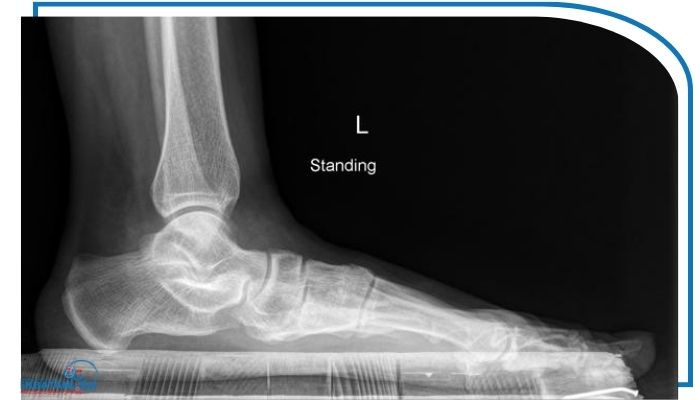

در مواردی که شدت تغییرات بیشتر باشد یا پزشک بخواهد محور استخوانی پا و زانو را با دقت بیشتری ارزیابی کند از روش‌های عکس انحراف زانو مانند اشعه X یا MRI استفاده می‌شود. رادیوگرافی معمولاً در حالت ایستاده انجام می‌شود تا زاویه بین استخوان ران و ساق به‌وضوح مشخص گردد. اگر در تصویرزانوها به سمت داخل متمایل باشند نشان‌دهنده ژنووالگوس یا همان زانوی ضربدری است و در صورت خم شدن زانوها به سمت خارج وضعیت ژنوواروم (زانوی پرانتزی) دیده می‌شود. در برخی موارد نیزMRI برای بررسی دقیق‌تر غضروف‌ها رباط‌ها و مفاصل زانو انجام می‌شود تا اثرات ناشی از صافی کف پا بر ساختار داخلی زانو به ‌طور کامل مشخص شود.